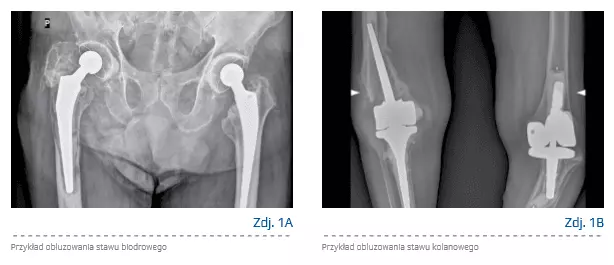

Aseptyczne obluzowanie jest częstym powikłaniem, zmniejszającym komfort życia pacjentów. W porównaniu z innymi komplikacjami, których diagnostyka z reguły nie stwarza znacznych problemów, mechanizmy leżące u podstaw aseptycznego obluzowania rozwijają się na przestrzeni lat, a objawy i dyskomfort występują późno [17].

Udoskonalone modele protez i lepsza technika operacyjna rozwinięte w okresie ostatnich dekad pozwoliły na zmniejszenie występowania poważnych powikłań septycznych, zwichnięć oraz złamań. Jednak częstość aseptycznego obluzowania pozostaje na wysokim poziomie i zgodnie z danymi stanowi przyczynę 63% operacji rewizyjnych [18]. Procesy leżące u podstaw aseptycznego obluzowania komponentu są złożone. Można wyróżnić czynniki fizyczne i biologiczne [19]. Pierwszym etapem jest wytrącanie się w stawie i okolicznych tkankach miękkich cząsteczek zużycia pochodzących z powierzchni artykulacyjnych protezy i jej innych elementów. Część badań wykazała, że rodzaj immunologicznej odpowiedzi komórkowej jest zależny od kształtu i wielkości tych cząsteczek [20, 21].

Wytrącające się cząsteczki indukują odpowiedź prozapalną okolicznych tkanek [23]. Pierwszy etap przeciwzapalnej odpowiedzi immunologicznej polega na formowaniu tkanki włóknistej otaczającej implant. Cząsteczki implantu wywołują lokalny proces zapalny w obrębie sztucznego stawu. Rekrutowane są liczne komórki odpowiedzi immunologicznej: fibroblasty, makrofagi, limfocyty, neutrofile oraz osteoklasty. Podstawowym procesem, leżącym u podstawy osteolizy i obluzowania jest aktywacja osi NF-κB (RANK)/RANK ligand (RANKL) aktywowanej przez ekspresję osteoprotegryny, RANK, RANKL w okołoprotezowych zapalnych złogach [17]. Wszystkie wspomniane procesy prowadzą w efekcie do obluzowania implantu, dolegliwości bólowych i dyskomfortu chorego. Czynniki ryzyka aseptycznego obluzowania zestawiono w tabeli 1, przykłady obluzowania w przypadku stawu biodrowego i kolanowego przedstawiono odpowiednio na zdjęciach 1A i 1B.